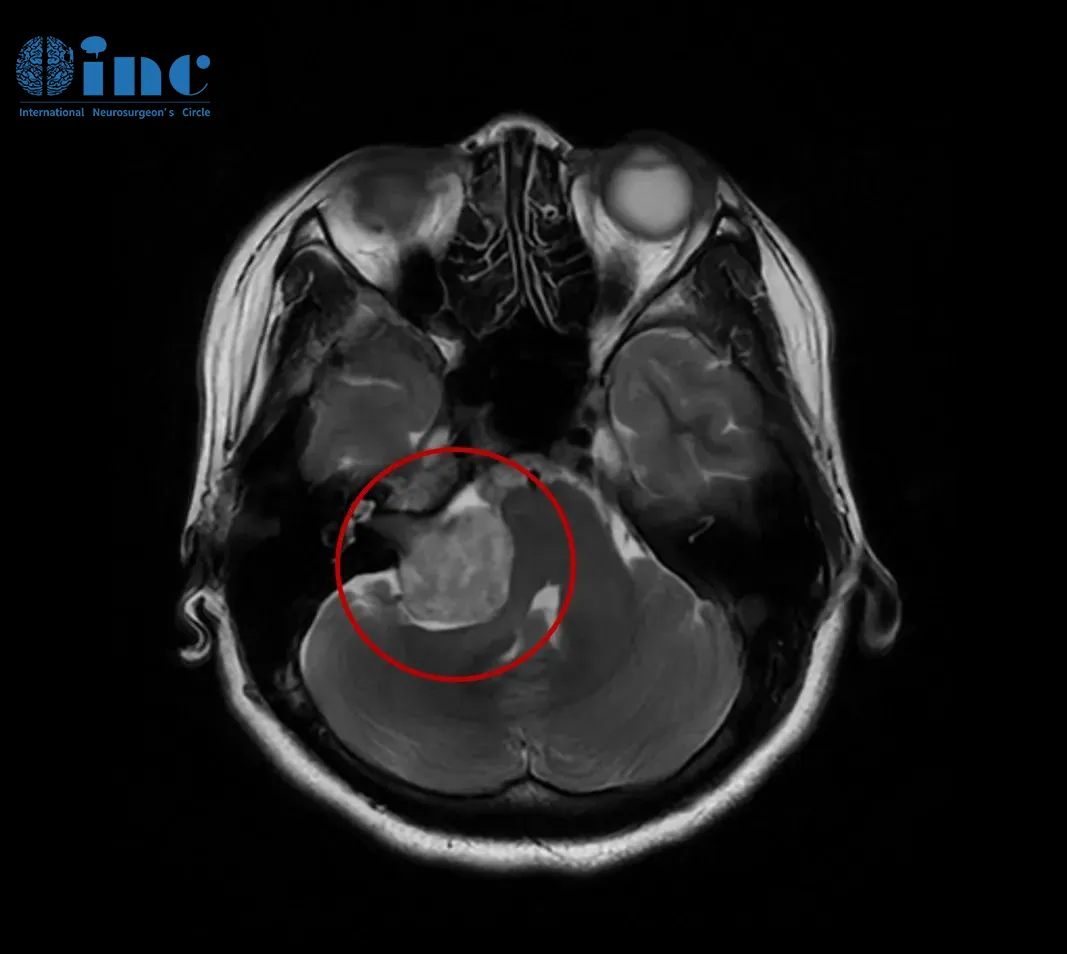

這次,她做了頭顱核磁共振(MRI)檢查,結(jié)果終于揭示了病因——右側(cè)CPA區(qū)前庭神經(jīng)鞘瘤。腫瘤最大直徑約35毫米(包括內(nèi)聽(tīng)道內(nèi)的部分),已經(jīng)壓迫到腦干,導(dǎo)致橋腦及右側(cè)橋臂受壓,四腦室變形。

聽(tīng)神經(jīng)瘤(前庭神經(jīng)鞘瘤)影像